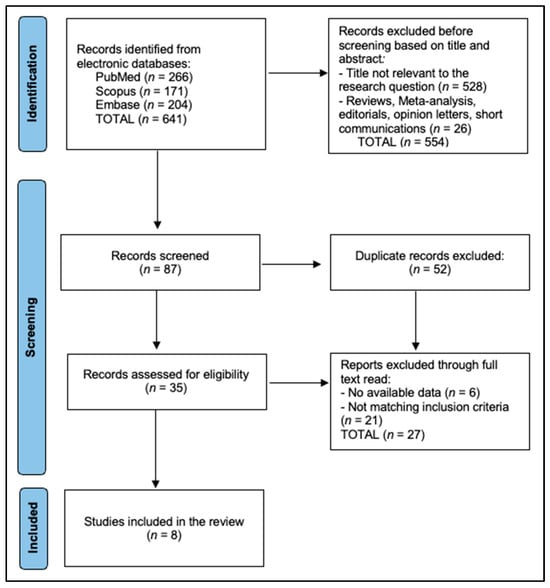

The PubMed strategy, combining MeSH and free-text terms (“stackable” OR “sequential template” OR “magnetic guide”) AND (“full arch” OR “edentulous”) AND (“implant”). The final search (26 June 2025) retrieved eight studies eligible for inclusion, as presented in Figure 1.

Figure 1.

PRISMA flowchart.